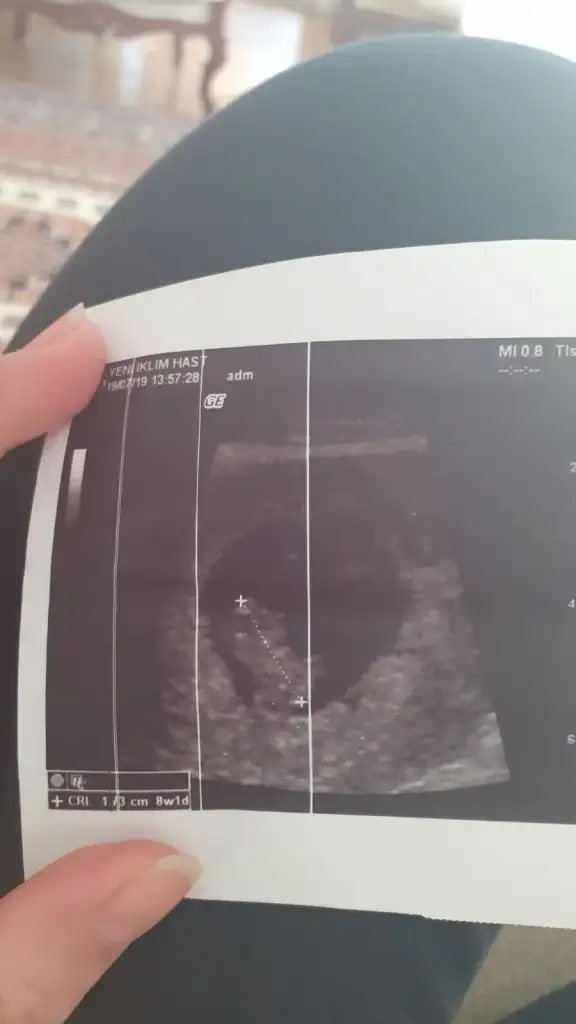

Şimdi ablam hamile 9+1 :)

Bebeğin 8+1 ultrason resmini yolluyorum cinsiyet tahminlerinizi merakla bekliyorum :)

Evet canım burada da tahmin yaparlar belki. Evet tahminim tutmuş saglıkla gelsinAnladım canım o halde diğer konuya yazıyorum orda daha küçük ultrason resmiyle tahmin yapılıyordu

Evet tuttu canım zaten bebek de 11+3te kendisini gösterdiEvet canım burada da tahmin yaparlar belki. Evet tahminim tutmuş saglıkla gelsin